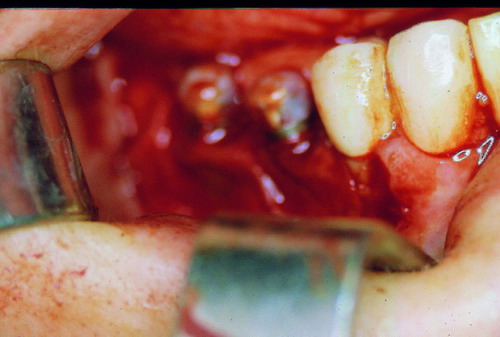

LA OCLUSIÓN MUTUAMENTE PROTEGIDA ES UN VIEJO CONCEPTO QUE CONSISTE EN LA MUTUA INTERACCIÓN DE LOS DISTINTOS GRUPOS DENTARIOS ENTRE SI. DE ESTA FORMA, LA TABLA PREMOLAR / MOLAR DE AMBOS HEMIMAXILARES ANTAGONISTAS, DETIENEN EL CIERRE MANDIBULAR EN CÉNTRICA, LOS CANINOS DISCLUYEN LAS PIEZAS POSTERIORES DURANTE LAS TRANSTRUSIONES, Y EL GRUPO INCISIVO LO MISMO DURANTE LAS PROPULSIVAS. SIN EMBARGO, DICHO CONCEPTO ES LIMITADO A LAS PIEZAS DENTARIAS, SIN TENER EN CONSIDERACIÓN LA IMPORTANTE FUNCIÓN QUE RECAE SOBRE LA ATM Y EN EL SOPORTE DE PRESIONES DURANTE ESTA DINÁMICA. ES ASI QUE EN EL AÑO 1981, EL DR. ANIBAL ALONSO GENERA EN LA CIUDAD DE BUENOS AIRES UN CONCEPTO MAS AMPLIO QUE DENOMINÓ : OCLUSION MUTUAMENTE COMPARTIDA. REF I EN EL QUE AMPLÍA EL CONCEPTO ANTERIOR, HACIENDO PARTÍCIPE A LA ATM EN LA MISMA. CUANDO EXISTE CARENCIA DE PIEZAS DENTARIAS POSTERIORES, YA SEA DE UN SOLO LADO O DE AMBOS , EL CIERRE MANDIBULAR ES DETENIDO POR LAS PIEZAS RESTANTE, FORZANDO A LA ATM A SOPORTAR PRESIONES MUY SUPERIORES A AQUELLAS PARA LAS QUE ESTA PREPARADA. FIG1 FIG2 FIG3 LUEGO DEL ESTUDIO CLÍNICO DE RIGOR, DONDE SE EVALÚA RADIOGRÁFICA Y PERIODONTALMENTE, SE PROCEDE A TOMAR MODELOS DE ESTUDIO Y MONTAR EN ARTICULADOR SEMIAJUSTABLE, SOBRE EL CUAL SE REALIZA UN ENCERADO PROGRESIVO DE DIAGNÓSTICO, A PARTIR DEL CUAL SE CONFECCIONA UN JUEGO COMPLETO DE PROVISIONALES DE AMBAS ARCADAS , INCLUYENDO LAS PIEZAS FALTANTES. SE ABORDA EL CASO YA QUIRÚRGICAMENTE DONDE EN UNA PRIMERA ETAPA SE TALLAN PRIMARIAMENTE LAS PIEZAS DENTARIAS Y SE PROCEDE, EXODONCIANDO EL INCISIVO CENTRAL SUPERIOR DERECHO, A REALIZAR UNA ROG(REGENERACIÓN ÓSEA GUIADA), PARA INMEDIATAMENTE INSTALAR PARTE DE NUESTROS PROVISORIOS EN LA GUIA ANTERIOR. SE ADAPTAN A LOS SECTORES POSTERIORES LAS PRÓTESIS REMOVIBLES QUE PORTABA, Y SE ESPERAN CUATRO MESES, AL CABO DE LOS CUALES SE REALIZA UN ESTUDIO CON DENTASCAN, MEDIANTE EL USO DE UNA FÉRULA RADIOLÓGICA CON TUBOS METÁLICOS , QUE NOS SERVIRÁ TAMBIÉN DE GUÍA QUIRÚRGICA. PROCEDEMOS ENTONCES A LA IMPLANTACIÓN DE LOS SECTORES EDÉNTULOS MEDIANTE IMPLANTES ROSCADOS Y TÉCNICA SEMI SUMERGIDA. TRANSCURRIDAS OCHO SEMANAS OBSERVAMOS UNA CORRECTA SALUD PERIMPLANTARIA, Y REALIZAMOS LA INSTALACIÓN DE LOS ABUTTMENTS ALCANZAMOS ENTONCES EL PUNTO EXACTO DONDE DEBEREMOS COMENZAR A RECONTRUIR EN FORMA PERMANENTE. PAZ DEL SISTEMA: CENTRICIDADARTICULAR-PAZ MUSCULAR-ESTABILIDAD- -ACOPLAMIENTO. BASES FUNDAMENTALES DE LA OCLUSIÓN ORGÁNICA FIG41 FIG42 PROCEDEMOS NUEVAMENTE A TOMAR IMPRESIONES, EN ESTE CASO DEFINITIVAS , MONTAR NUEVAMENTE EN ARTICULADOR, Y CONSTRUIR LAS RESTAURACIONES PERIFÉRICAS TOTALES EN BASE A PORCELANA SOBRE ORO GALVANIZADO. REF. II SOBRE LAS MISMAS TERMINADAS Y YA EN BOCA, CHEQUEÁMOS TODOS LOS ELEMENTOS QUE CONSTITUYEN UNA REHABILITACIÓN ORAL INTEGRAL, DESDE LA SALUD ENDODONTICA DE PIEZAS TRATADAS O NO, LA SALUD PERIODONTAL, EL AJUSTE PERIFÉRICO DE LAS RESTAURACIONES, LA ESTABILIDAD EN LA ATM, Y LAS FUNCIONES OCLUSALES, CHEQUEOS ESTOS QUE SE REPETIRAN EN CADA UNO DE LOS CONTROLES POST OPERATORIOS. FIG46 FIG47 FIG48 FIG66 FIG67 REFERENCIAS: REF I: OCLUSIÓN Y DIAGNÓSTICO EN REHABILITACIÓN ORAL REF. II ELECTROFORMACIÓN EN ODONTOLOGÍA RESTAURADORA.